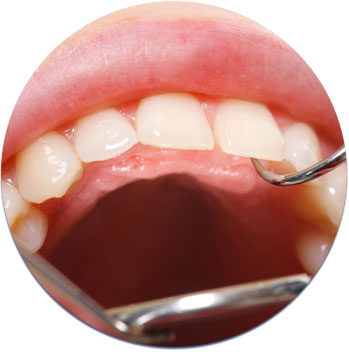

Dexis Intraoral Camera

As discussed, digital x-rays are a very important part of diagnosing dental disease and developing treatment plans. At the same time, being able to capture HD images at up to 10x magnification is equally important. Whether it is decay, gum disease or a cracked tooth, these images allow us to show you what we are seeing in your mouth. Our intraoral camera also helps us enhance communication and claims approval with dental insurance providers.